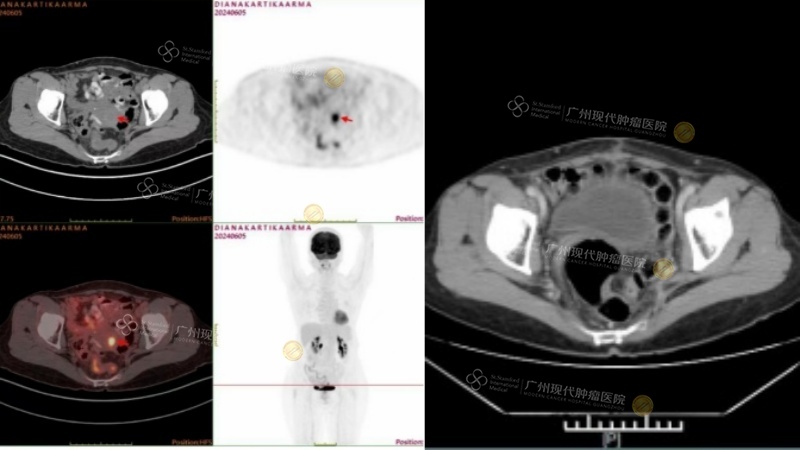

Когда Диана впервые прибыла в больницу, я принял ее и стал ее лечащим врачом. Я до сих пор помню, что когда ее впервые положили в больницу, она была в плохом настроении и истощена. Я назначила ей ряд обследований, и через два дня после поступления пришли результаты анализов: онкомаркер CA19-9 повысился до 49,58 *Ед/мл, а ПЭТ-КТ показала опухоль размером 1,5x1,2x2,9 см в шейке матки. На основании анамнеза и результатов обследования поставлен диагноз: низкодифференцированная аденокарцинома шейки матки IB2 стадии. Принимая во внимание стадию опухоли, степень дифференцировки и общее состояние пациентки, команда МДТ после достаточного обсуждения и анализа пришла к выводу, что наиболее подходящим вариантом лечения является минимально инвазивная гистерэктомия в сочетании с интервенционным лечением. Целью является полное удаление опухолевых поражений, а также дальнейший контроль заболевания посредством интервенционного лечения и снижение риска рецидива.

После нескольких интервенционных методов лечения 18 октября 2024 года компьютерная томография показала, что опухоль «полностью исчезла», а опухолевые маркеры практически вернулись к нормальным уровням. Диана также начала набирать вес, а качество ее сна и аппетит значительно улучшились.

КТ до лечения КТ после лечения